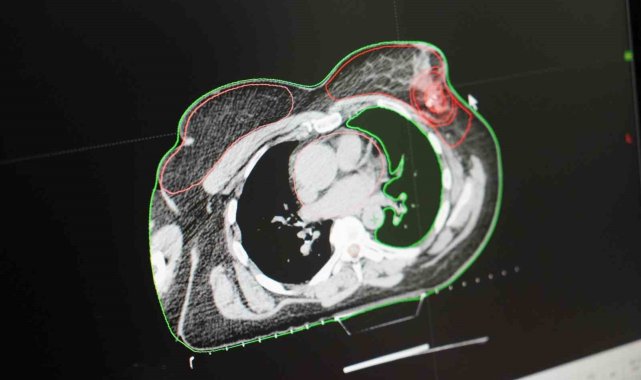

SAMSUN (İHA) – Kadınlarda en çok görülen kanser türlerinin başında gelen 'meme kanseri'nde tedavinin mümkün olduğunu belirten Medikal Onkoloji Uzmanı Prof. Dr. İdris Yücel ve Radyasyon Onkolojisi Uzmanı Dr. Özge Özdemir, hastaların dikkat etmesi gereken hususları ve uyması gereken noktaları açıkladı.Meme kanseri hem Türkiye'de hem de dünyada kadınlarda en sık görülen kanser türlerinden biri olarak dikkat çekiyor. Erkeklerde de görülen meme kanseri ile ilgili olarak ilk evreden son evreye kadar süreçte uyulması gereken hususlar ve tedavi yöntemleri hakkında bilgiler veren Medicana Sağlık Grubu doktorlarından Prof. Dr. İdris Yücel ve Uzm. Dr. Özge Özdemir, önemli açıklamalarda bulundu."Meme kanseri, tedavi süreci uzun ama iyileştirilebilir bir hastalık türüdür"Sadece bir tedavi yöntemi ile değil birçok tedavi yöntemi ile meme kanserinin değişik evrelerine tedavi uygulayabildiklerinin altını çizen Medicana International Samsun Hastanesi Medikal Onkoloji Uzmanı Prof. Dr. İdris Yücel, "Meme kanserinin tedavi süreci biraz karmaşıktır. Uzun bir süreçtir. Hastaların sabırla bu süreci izlemesi ve doktorlarının tavsiyelerini ve takiplerini aksatmamaları gerekiyor. Tedavi süreci biyopsi ile tespitin ardından hastalığın evresi belli ediliyor. Tümör memede midir, koltuk altına gitmiş midir, karaciğer, kemik gibi organlara gitmiş midir? Bunlara bakılır. Eğer başka organlara gitme durumu yoksa olay sadece memedeyse ve küçük bir tümörse doğrudan cerrahiye gönderebiliyoruz. Çoğu kez tümör büyüyor ve başka yerlere sıçrıyor. Böyle olursa önce tedaviyle başlıyoruz. Kemoterapide evre küçülürse hastayı cerrahiye veriyoruz. Cerrahi sonrası patoloji raporundaki özelliklere göre uzun bir süreç olan koruyucu tedaviler uyguluyoruz. Hormona duyarlı hücreler söz konusu ise o zaman hastaya endokrin tedavi veriyoruz. Bu 5-10 yıl gibi bir zamana yayılabiliyor. Meme kanserinin bazı özel tiplerinde immünoterapi yapabiliyoruz. Tümörün ve hastanın genel özelliklerine göre bazı akıllı ilaç tedavileri var. Oldukça komplike, faydası çok fazla ve beli bir kalıpta her hastayı tedavi edemiyorsunuz. Her hastanın tedavisini o hastaya özel olarak planlıyoruz. Meme kanseri tedavisinde cerrahi, onkoloji, radyasyon onkolojisi, hormonoterapi ve immünoterapi gibi bölümlerde tedavi gerçekleştiriliyor. Tedavi süreci uzun ama iyileştirilebilir bir hastalık türüdür meme kanseri" dedi."Radyoterapi güvenilir bir tedavi yöntemidir"Meme kanserinde radyoterapinin önemine değinen Radyasyon Onkolojisi Uzmanı Dr. Özge Özdemir ise, "Meme kanseri, kadın kanserlerinin 3'te 1'ini oluşturmaktadır. Bu nedenle farkındalık önem arz ediyor. Radyasyon onkologları olarak tedavinin her aşamasında hastaların yanındayız. Hem cerrahi hem kemoterapi hem de radyoterapi bir ekip olarak işbaşındayız. Meme kanserinin radyoterapisini erken evrede meme koruyucu cerrahi yapılmış olgularda daha sonra meme ve lenf bölgesine vaka kontrolü sağlamak yani nüksleri engellemek ve hastanın sağ kalımını sağlamak amacıyla uygulamaktayız. Yine lokal ileri hastalıkta sistemik kemoterapi sonrası uygulanan cerrahinin ardından nüksleri engellemek ya da kemoterapi sonrası cerrahi uygun olmayan vakalarda tümörü küçültmek amaçlı radyoterapi yapıyoruz. Ayrıca beyin metastazlarında, kemik metastazlarında ağrıyı gidermek, yumuşak doku metastazlarında kitlenin ağrısını, kanamasını, kokusunu gidermek amaçlı da palyatif radyoterapi yapmaktayız. Meme kanserinde radyoterapi her aşamada olmazsa olmaz bir yaklaşımdır. Radyoterapi alanındaki bilimsel ve teknolojik gelişmeler sayesinde hedeflediğimiz dozu uygulayacağımı volume uygun, yan etki profili en az olacak şekilde uygulayabilmekteyiz. Bu açıdan radyoterapi güvenilir bir tedavi yöntemidir. Meme kanseri farkındalığı hayatımızda olsun ama meme kanseri hayatımızda olmasın" diye konuştu.Uzmanlar ayrıca meme kanserinin çok önemli bir halk sağlığı sorunu olduğuna dikkat çekerek, her kadının kendi meme muayenesini yapabilecek düzeyde bilgi sahibi olmasının ve düzenli doktor kontrolüne gitmesinin zorunlu olduğunu söylediler.